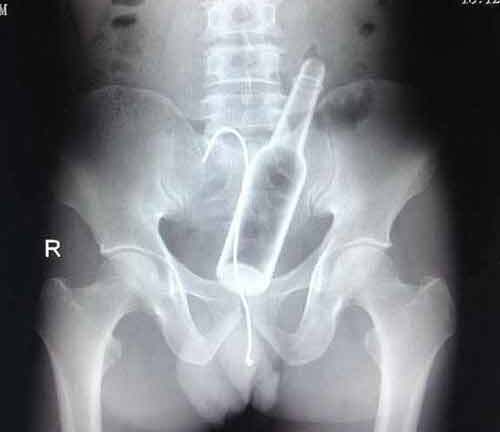

Ngay sau đó, anh Q được người dân đưa đi bệnh viện cấp cứu, kết quả khám xét cho thấy, anh Q bị một vết thương thấu bụng gây thủng ruột non, tỉ lệ thương tích 54\%.